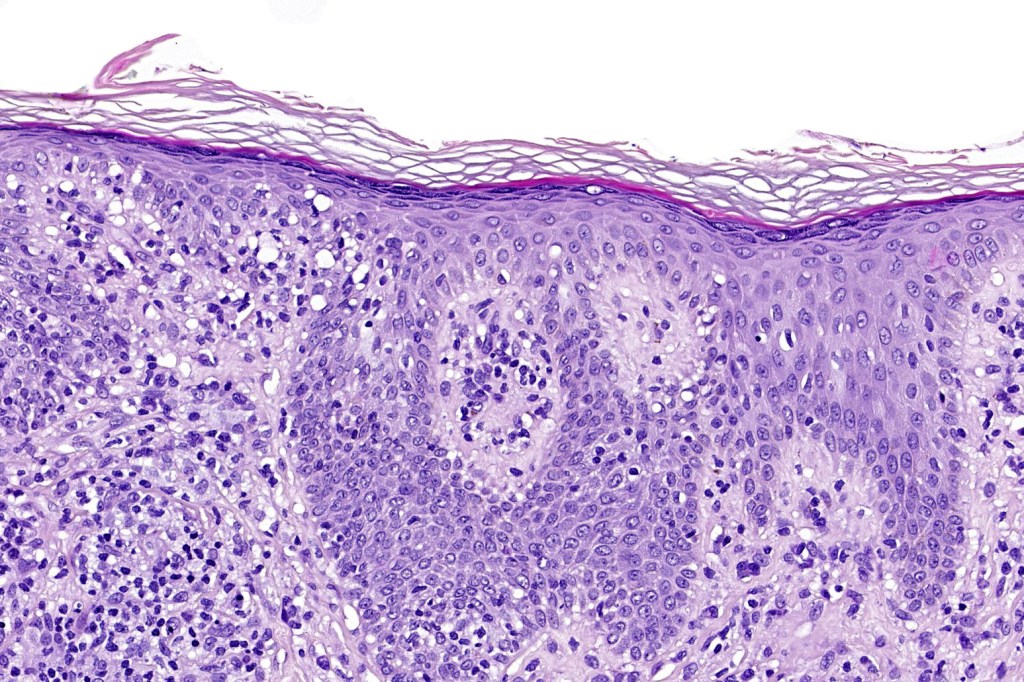

Histological features

The histological hallmark of mycosis fungoides is the presence of large atypical lymphocytes with a convoluted/cerebriform nuclear border (Sézary cells). These may be found at the epidermal-dermal jnuction and as collections within the epidermis (Pautrier microabscess). These are most easily found in plaque stage disease. The epidermal component can be subtle in patch stage disease and is often lost in tumor stage dsease. The classification into patch, plaque & tumor stage disease is less helpful histologically as the features merge from one to the other. It is all a matter of degree.

Plaque Stage Disease

•Compact hyperkeratosis & patchy parakeratosis

•Acanthosis

•Psoriasiform hyperplasia common

•Epidermotropism is often marked with conspicuous Pautrier microabscesses

•Superficial band-like dermal infiltrate of atypical lymphocytes, eosinophils, plasma cells & histiocytes